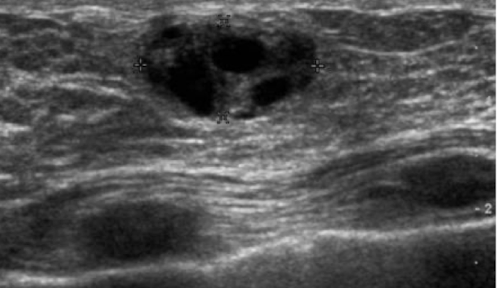

oil cyst